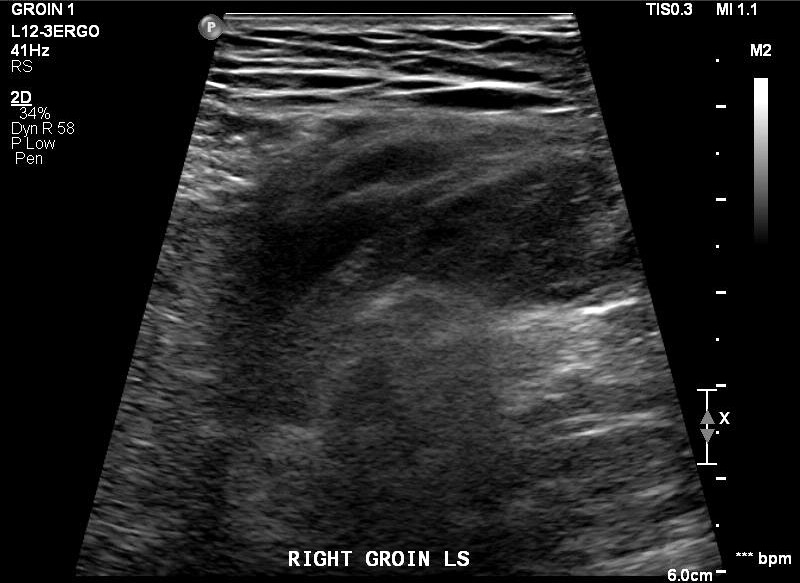

After seeing an Urologist, he suspect it is Inguinal Hernia and ordered an ultrasound scan in June 2025.

Ultrasound scan confirmed a 2.3cm hole in my tummy.